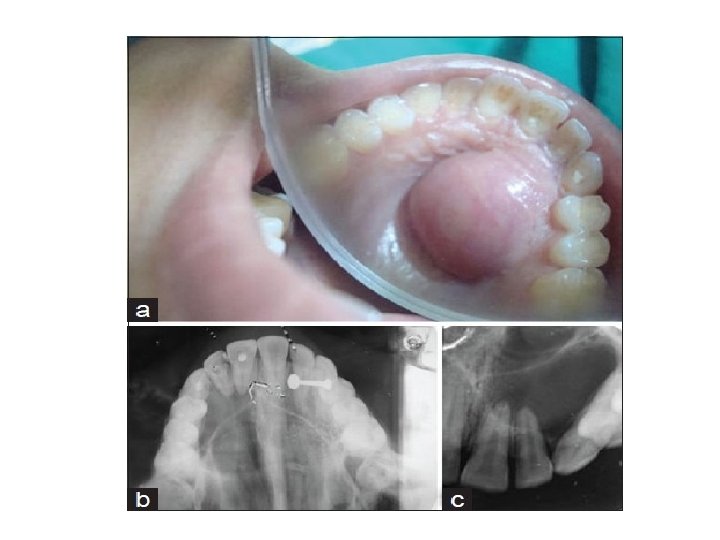

Hyperplastic pulpitis (pulp polyp) • A form of irreversible pulpitis, is the result of growth of chronically inflamed young pulp into occlusal surfaces • Usually asymptomatic. reddish cauliflower-like growth of connective tissue. • Attributed to a low- grade chronic irritation

Hyperplastic pulpitis (pulp polyp) It is occasionally associated with signs of irreversible pulpitis such as spontaneous pain. The teeth respond within normal limits when palpated or percussion. The threshold to electrical stimulation is similar to that found with normal pulp.

Hyperplastic pulpitis (pulp polyp) Microscopically: • A complex of new capillaries • proliferating fibroblasts & inflammatory cells. • Sensory nerve elements are almost totally absent near the surface, in contrast to the rich innervations of an exposed non-hyperplastic pulp. • Treatment: requires pulpectomy, R. C. T or extraction.